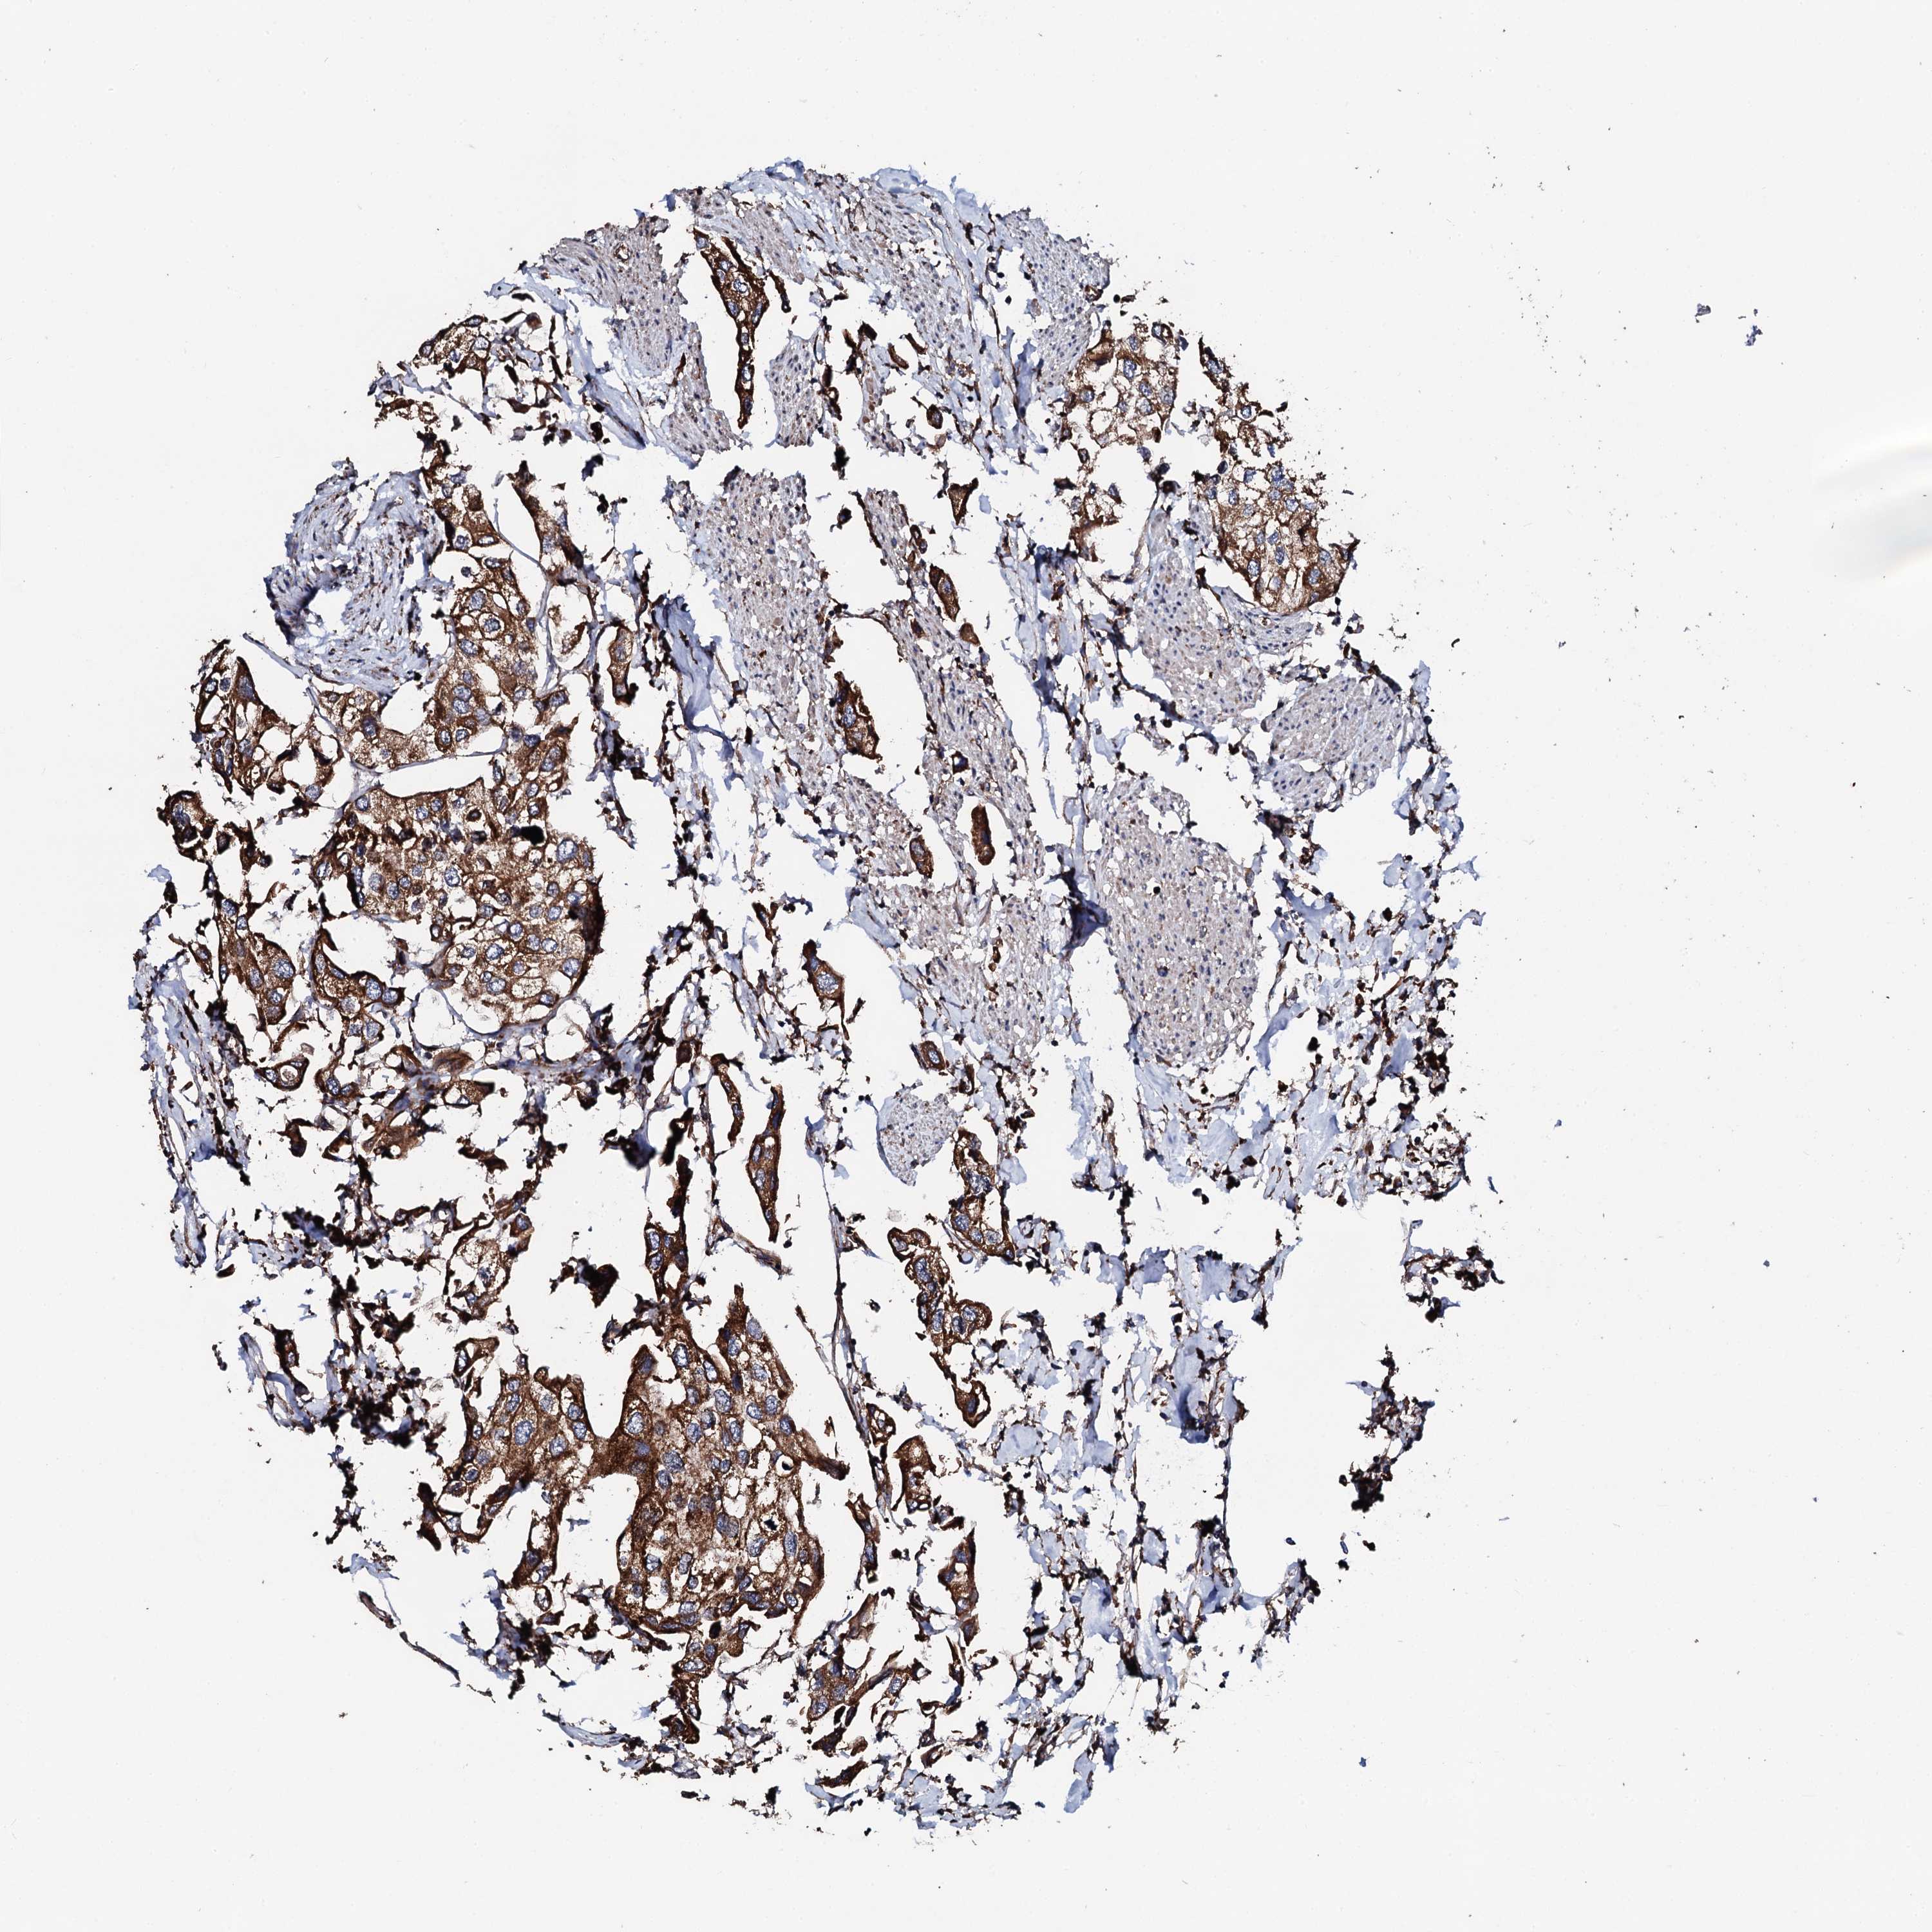

UROTHELIAL CANCER - Protein expressioni

A mouse-over function shows sample information and annotation data. Click on an image to view it in a full screen mode. Samples can be filtered based on level of antibody staining by selecting one or several of the following categories: high, medium, low and not detected. The assay and annotation is described here.

Note that samples used for immunohistochemistry by the Human Protein Atlas do not correspond to samples in the TCGA dataset.

Antibody stainingi

Antibody staining in the annotated cell types in the current human tissue is reported as not detected, low, medium, or high, based on conventional immunohistochemistry profiling in selected tissues. This score is based on the combination of the staining intensity and fraction of stained cells.

Each image is clickable and will lead to virtual microscopy that enables deeper exploration of all samples and also displays staining intensity scores, fraction scores and subcellular localization as well as patient and tissue information for each sample.

Antibody HPA039377

Antibody HPA040375

Urothelial carcinoma, High grade

Urothelial carcinoma, Low grade